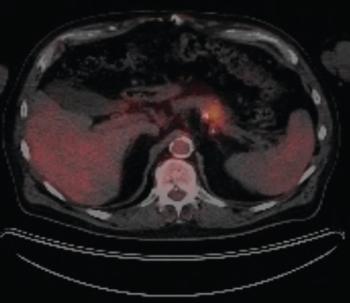

ByMehmet Sitki Copur, MD, FACP,Geoffrey A. Talmon, MD,Whitney Wedel, MD,Jonathan D. Hart, MD,Shaheed Merani, MD, PhD,Luciano M. Vargas, MD Pancreatic ductal adenocarcinoma is a disease marked by high rates of mortality, with only about 7% of patients surviving 5 years after diagnosis. Here, the authors present a demonstrative case and review the available data on hereditary and familial PDAC.